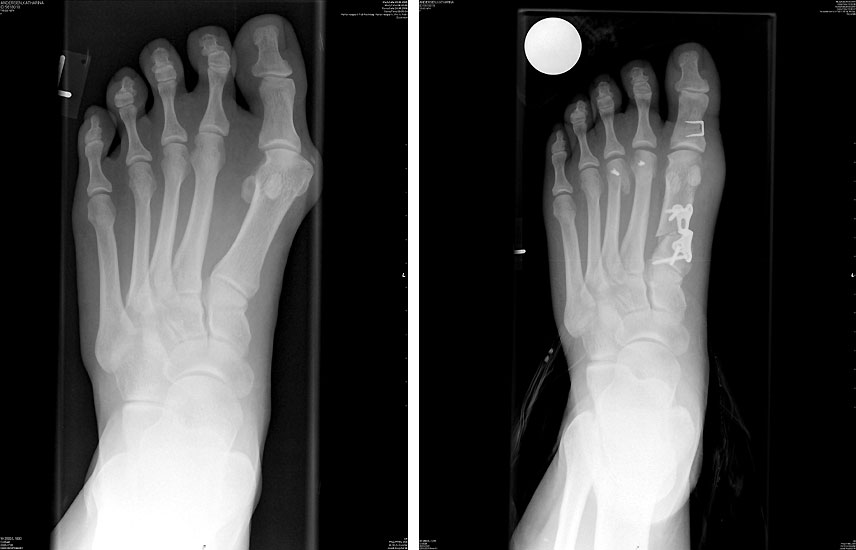

Operationsprinzip

• Beseitigung der Druckschmerzen über dem Großzehenballen durch Korrektur des Spreizfußes.

• Beseitigung einer Transfermetatarsalgie durch Wiederherstellung der Lastaufnahme des Metatarsale 1.

• Korrektur der Valgusfehlstellung der Großzehe und Verhinderung der Verdrängung der zweiten Zehe.

• Resektion der Pseudoexostose, Reposition des Großzehengrundgelenkes durch ein Release der lateralen Gelenkkapsel, Reposition des MTK 1 durch Ablösen der Sesambeinaufhängung, Wiederherstellung des physiologischen Intermetatarsalewinkels durch eine proximale Verschiebeosteotomie.

• Hallux valgus Fehlstellungen mit einem erhöhten Intermetatarsale Winkel 578.

• Röntgenaufnahmen des Fußes in 2 Ebenen, a.p. stehend

Ergebnisse

Die OP Methode hat sich als Standardeingriff bei größeren Hallux valgus Fehlstellungen etabliert. Der Intermetatarsale Winkel kann sehr gut korrigiert werden. Der Erste Strahl wird stabilisiert und kann wieder Last aufnehmen. Die Verwendung einer winkelstabilen Plattenosteosynthese zur Fixation einer proximalen Osteotomie am MT 1 hat sich bereits bewährt123, insbesondere auch mit der hier verwendeten TOM Platte (Thomas M. 2009). Die V-förmige Knochenschnittführung bietet eine zusätzliche Stabilität.